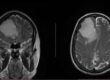

La simulación es un paso crucial, durante el cual se inmoviliza temporalmente el ojo del paciente con medicamentos. Utilizando imágenes avanzadas como resonancia magnética y tomografías, los médicos delinean con precisión el área que necesita tratamiento. Ahí es donde entra en acción el CyberKnife.

El CyberKnife, en conjunto con la camilla robótica Robocouch, conforma una plataforma sin igual en Centroamérica. Su precisión es insuperable, capaz de rastrear los movimientos milimétricos del paciente. Esta tecnología ha sido reconocida y se encuentra publicada, como la primera serie de pacientes tratados en Centroamérica por melanoma uveal utilizando Cyberknife, en la prestigiosa revista Oncology and Pathology. En este, los autores y lideres del proyecto, Dra. Raquel Benavides y el Dr. Alejandro Blanco respaldados por un equipo de médicos multidisciplinarios, describen su experiencia tratando con éxito a cuatro pacientes reportando una tasa de control del 100%, por dos años posterior a su tratamiento, desde ese entonces 16 pacientes han sido tratados de tumores malignos en el ojo.